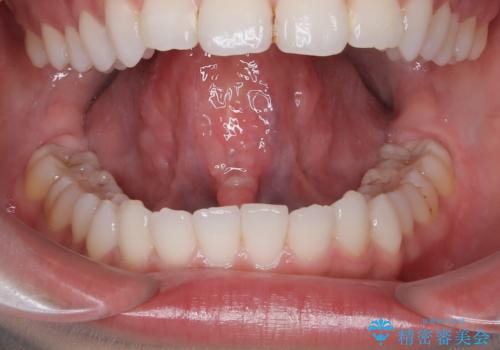

[滑舌を治したい] 舌の小帯の形成術

担当医 大元洋佑

![[滑舌を治したい] 舌の小帯の形成術の症例 治療前](https://seimitsushinbi.jp/wp/wp-content/uploads/2023/11/IMG_8451-500x350.jpg?v=1699614841)

![[滑舌を治したい] 舌の小帯の形成術の症例 治療後](https://seimitsushinbi.jp/wp/wp-content/uploads/2023/11/IMG_8901-500x350.jpg?v=1699614854)